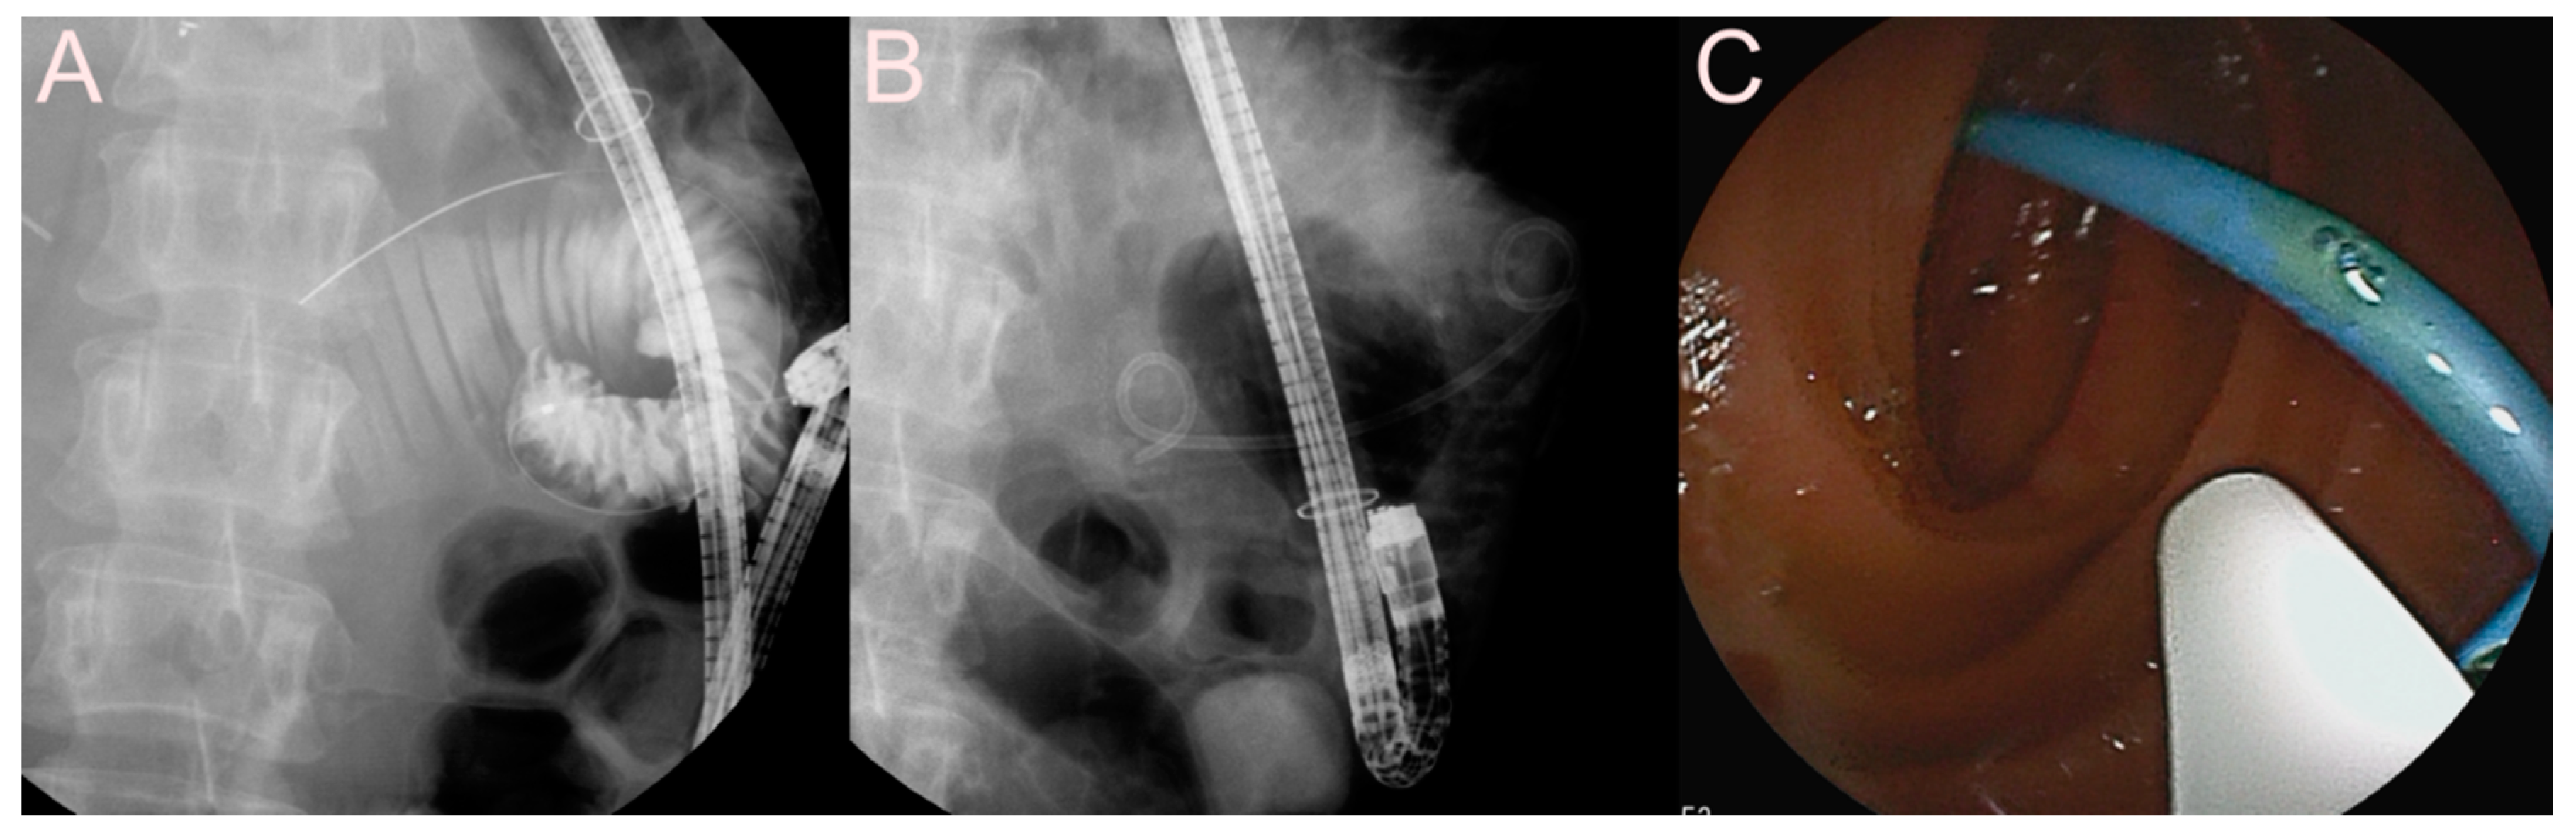

2.5. Stent for EUS-Guided Creation of Entero-Enteric Anastomosis